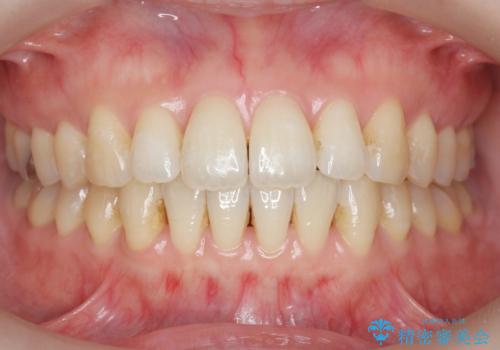

- 出っ歯に見える前歯を治したい、と矯正治療を希望され来院されました。

奥歯の噛み合わせに大きな問題はないので、目立つ前歯の角度・隙間を重点的に整え、審美的な歯並びを獲得できるよう計画します。

治療によりしっかりと前歯の角度が改善され、審美的な歯並びを手に入れることができました。